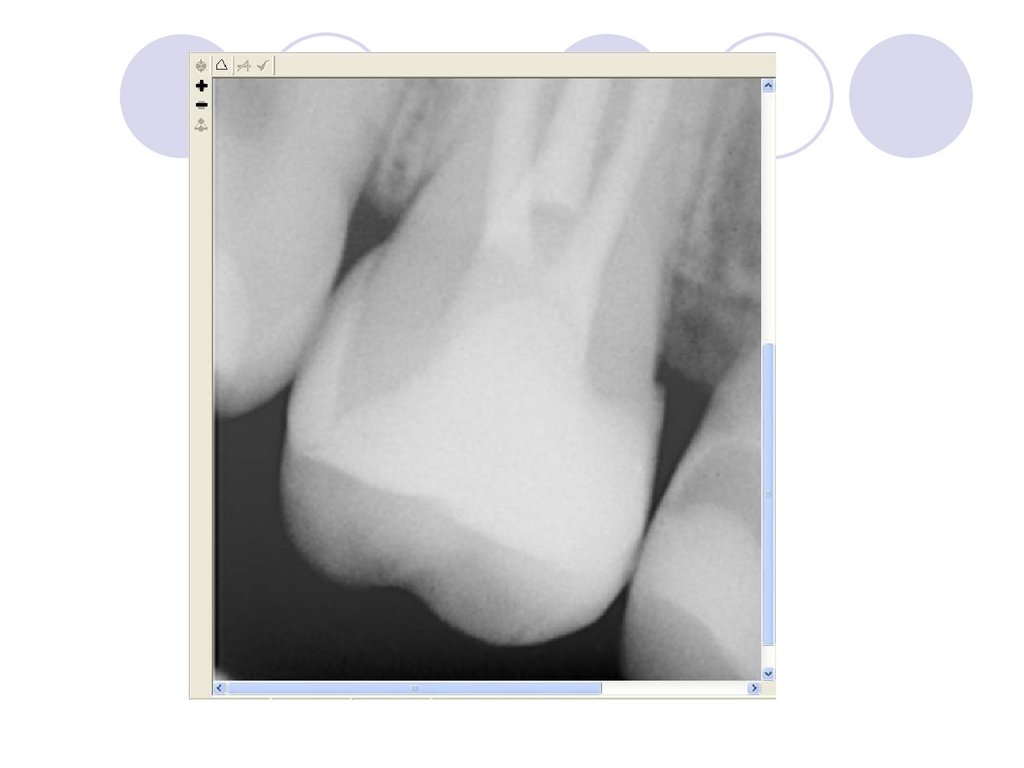

Перед изготовлением вкладки

необходимо тщательно обследовать

кариозную полость или дефект

твердых тканей зуба. Для более

четких представлений о топографии

пульпарной полости и ее

взаимоотношении с дефектом

коронки следует получить

рентгеновский снимок зуба.